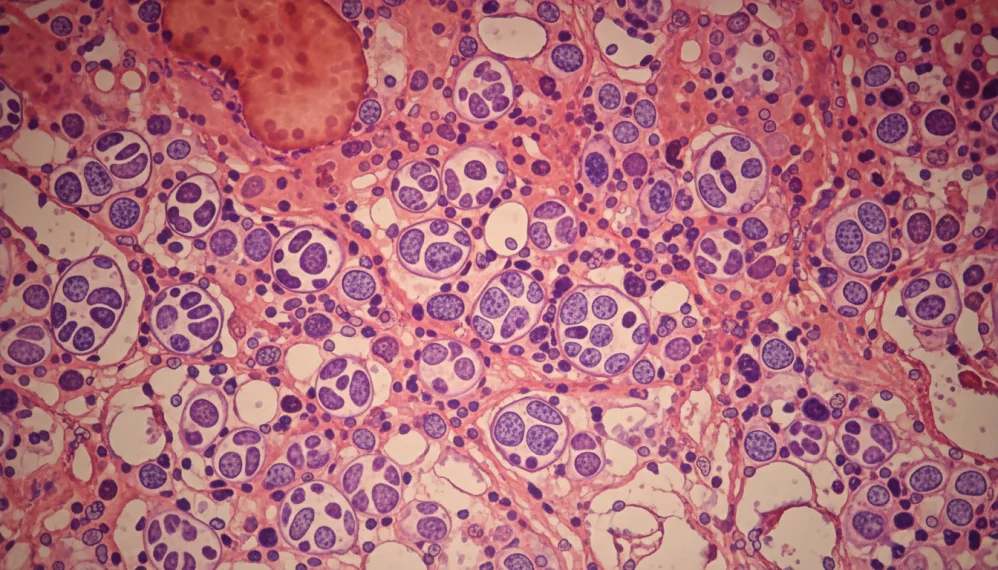

Aspiratia si biopsia maduvei osoase. Acest procedeu se face prin introducerea unui ac la nivelul osului cu aspirarea unei cantitati de os si maduva osoasa. Recoltarea se face din creasta iliaca (din osul soldului) sau din stern. Examinarea fragmentelor se face sub microscop pentru a evidentia semnele de cancer.

Pentru diagnosticul mielofibrozei cronice idiopatice se efectueaza anumite teste, pe langa hemoleucograma. Aceste teste includ: aspiratie si biopsie medulara, analize citogenetice si analiza sangelui periferic. Analiza sangelui periferic este un procedeu in care o picatura de sange recoltata din deget cel mai frecvent este analizata sub microscop si se cauta prezenta de celule rosii cu frome speciale, se determina numarul si tipul celulelor albe, numarul plachetelor si prezenta sau absenta celulelor blastice.